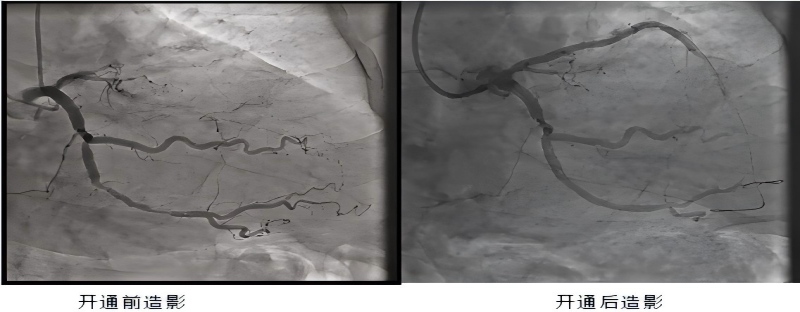

患者转入后随即进行了冠状动脉造影检查,造影结果显示:左前降支(LAD)自近段完全闭塞伴明显钙化!回旋支(LCX)远段狭窄90%,这是一种心血管内科专业的急危重症,意味着患者心脏的一大片区域长期处于严重缺血状态,随时有发生猝死的可能。由于患者前降支闭塞并伴有严重钙化,首先建议患者开胸搭桥,但患者家属坚决拒绝,坚持介入治疗。经充分论证、准备和沟通,心血管内二科介入团队遂冒着巨大风险为患者实施了冠脉介入手术。康振兴主任带领手术团队凭借精湛的技术,在IVUS辅助下,成功开通闭塞的前降支并在病变处植入了支架,同时于回旋支病变处植入支架,开通狭窄血管,重新建立了心脏的血液供应“生命线”。

目前,困扰患者半年的头晕症状和心前区不适感得到了明显改善,精神状态明显转好。患者及家属对我院医护人员精湛医术、高效的多学科协作能力表示了极大的赞誉和衷心的感谢。